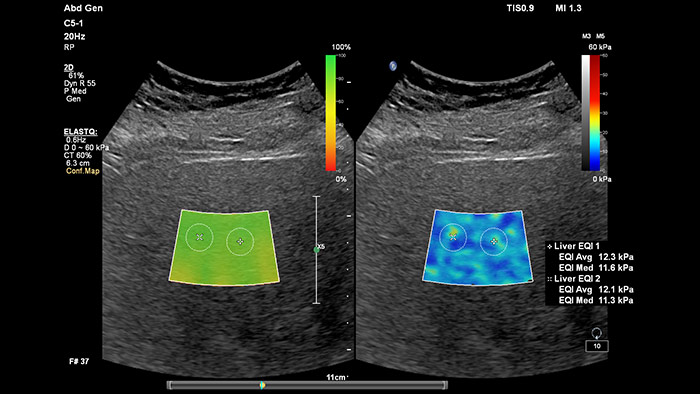

La elastografía por ultrasonidos de onda transversal ofrece un método no invasivo, reproducible y fácil de poner en práctica para evaluar la rigidez tisular. Los estudios realizados apuntan a que, en lugar de un costoso y doloroso procedimiento de biopsia, una sencilla exploración por ultrasonidos con elastografía de onda transversal podría convertirse en el procedimiento habitual para evaluar el estado de las enfermedades hepáticas. La elastografía por onda transversal de alto rendimiento de las imágenes con ElastQ incluye la evaluación cuantitativa de la rigidez tisular, codificada con colores, en extensas regiones de interés (ROI) en tiempo real. Las imágenes con ElastQ también ofrecen la posibilidad de efectuar mediciones retrospectivas en imágenes almacenadas; además, una exclusiva pantalla con un mapa de confianza emplea el análisis inteligente para ofrecer la garantía adicional de que las mediciones del usuario se han obtenido en zonas tisulares con una propagación adecuada de ondas transversales.

La medición de la rigidez hepática se obtiene en cuestión de segundos por medio de una sencilla exploración no invasiva.